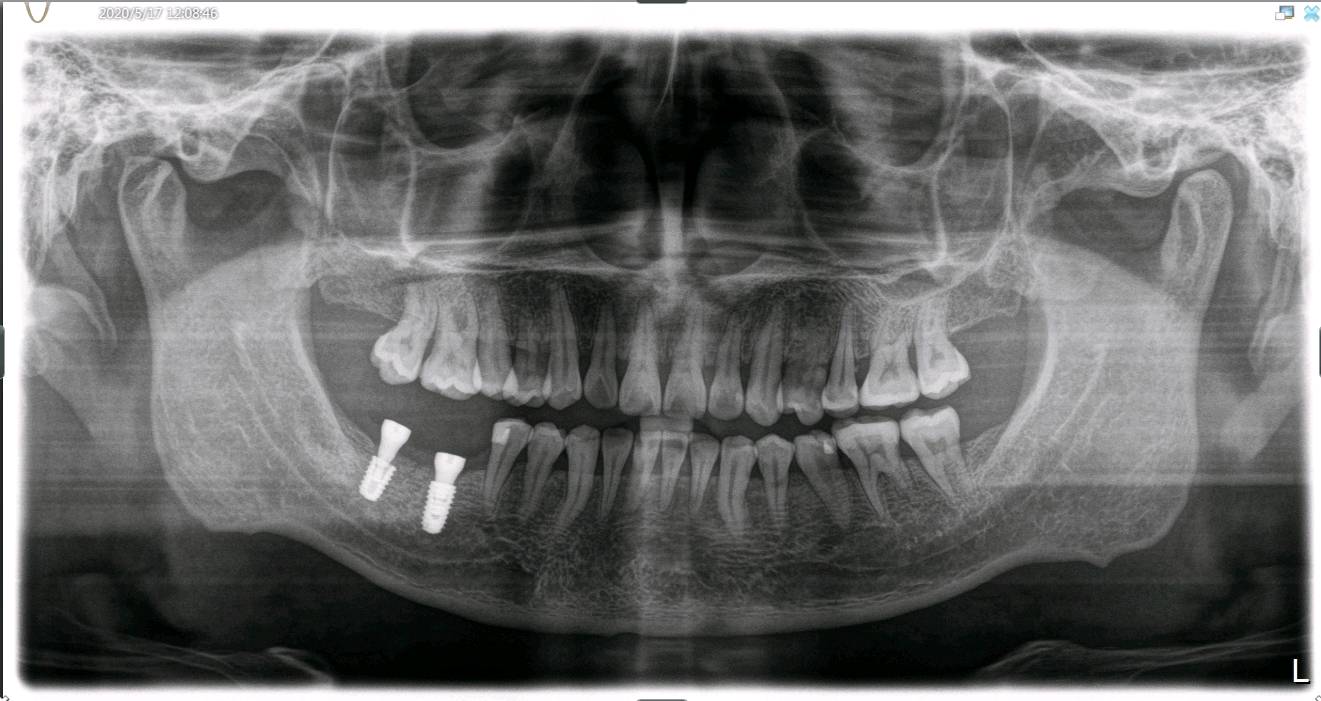

患者男,35岁,右下后牙缺失半年。口内检查:47牙体缺失,缺牙区牙槽嵴中度萎缩,无骨尖。颌龈距离约5mm。46松动+++,牙龈中重度退缩。X线示缺牙区骨密度良好。46牙槽骨吸收至根尖1/3。

治疗计划:46拔除+种植修复。47种植修复。

患者自愿选择皓圣种植体,46植入5.0*8.7mm型号。47植入5.1*7.2mm。并植入BIOSS骨粉和生物膜,CGF覆盖。定期复查,如期进行二期三期。恢复期咬合。其实很多人觉得缺颗牙齿没什么特别大的影响,其实不然,后牙单侧缺失,会导致患者偏侧咀嚼,长久下来会有大小脸的情况。而邻牙也会发生倾斜,对颌牙会伸长。对颌牙伸长会导致食物嵌塞而至其龋坏。长时间的牙体缺失可能会引起咬合的异常甚至关节的不适。

术前